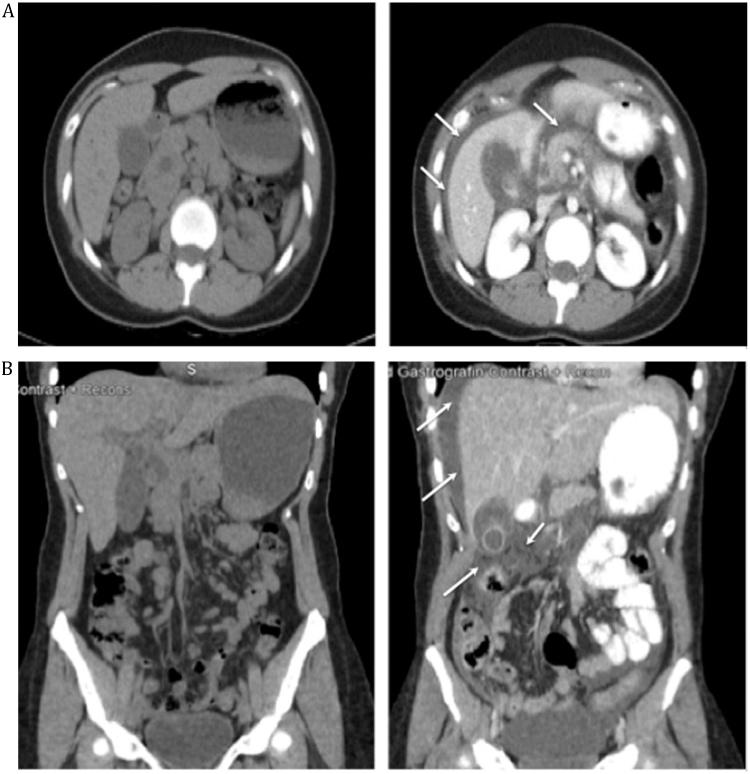

Herein, we describe the case of a 28 year-old female who suffered spontaneous common bile duct perforation while admitted for choledocholithiasis.

The perforation occurred while in-hospital, and extensive imaging and laboratory tests characterized the disease in detail. To our knowledge, this is the first report of spontaneous common bile duct perforation witnessed from pre-perforation through definitive management.